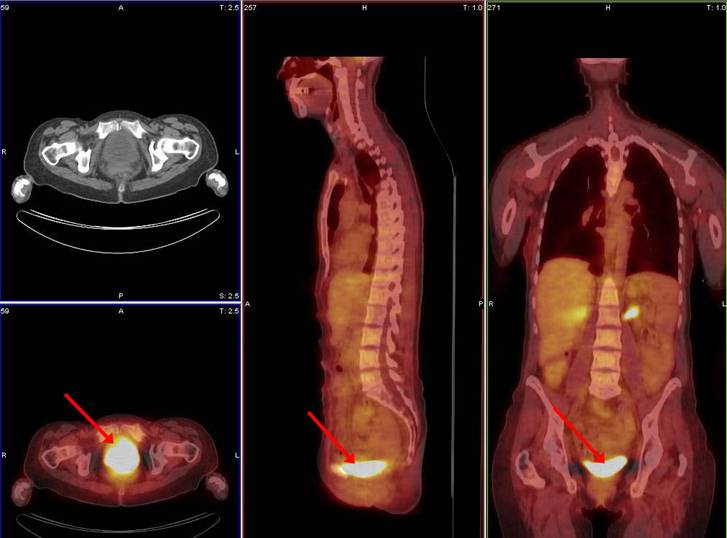

Void prior to imaging

Why is it important for the patient’s to void prior to scanning?

If the patient doesn’t empty their bladder before we scan the PET images, their bladder will be visibly ‘hot’ and interfere with the images